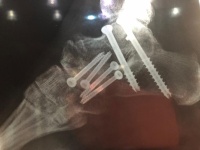

Pilar Cisneros Walk incluye accidentes de tráfico, dos operaciones y cinco pines en el tobillo – Cr Noticias